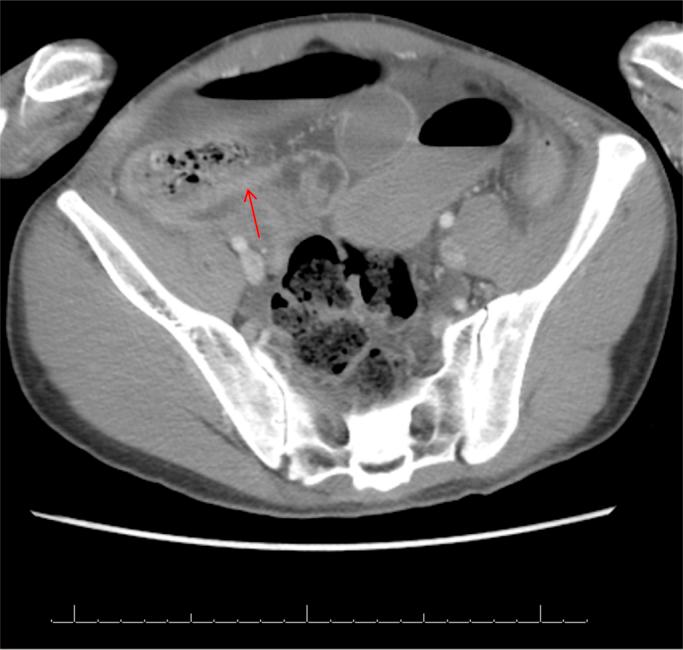

A 28-year-old male with no past surgical history, known to have severe mental retardation presented with anorexia. CT scan demonstrated dilated small bowel loops and intraluminal ileal mass with mottled appearance. At exploratory laparotomy, a bezoar was found impacted in the terminal ileum 5-6 inches away from the ileocecal valve and was removed through an enterotomy.

一名28岁男性,无既往手术史,已知患有严重智力障碍,出现厌食症状。CT扫描显示小肠肠袢扩张,回肠腔内有斑驳状肿物。在剖腹探查术中,发现一枚胃石嵌顿在距回盲瓣5 - 6英寸处的回肠末端,并通过肠切开术将其取出。

Bezoars are concretions of fibers or foreign bodies in the alimentary tract. Small bowel obstruction is one of common clinical symptoms. The typical finding of well-defined intraluminal mass with mottled gas pattern in CT scan is suggestive of an intestinal bezoar. The treatment option of bezoar is surgery including manual fragmentation of bezoar and pushing it toward cecum, enterotomy or segmental bowel resection. Thorough exploration of abdominal cavity should be done to exclude the presence of concomitant bezoars. Recurrence is common unless underlying predisposing condition is corrected.

胃石是消化道内纤维或异物的凝结物。小肠梗阻是常见的临床症状之一。CT扫描中典型的表现为边界清晰的腔内肿物伴有斑驳状气体影,提示为肠内胃石。胃石的治疗选择是手术,包括手动破碎胃石并将其推向盲肠、肠切开术或肠段切除术。应彻底探查腹腔以排除合并存在的胃石。除非纠正潜在的易感因素,否则复发很常见。